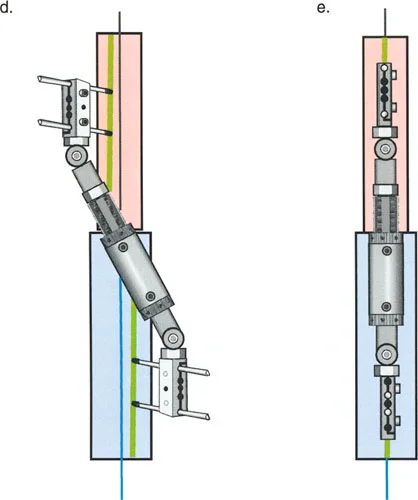

ومع ذلك، تعتمد هذه "المعجزة البيولوجية" بشكل كبير على الاستقرار الميكانيكي. إذا كان المثبت الخارجي شديد الصلابة، فقد لا يتكون العظم الجديد بشكل كافٍ؛ وإذا كان فضفاضًا جدًا، فإن قوى القص ستدمر الأوعية الدموية الدقيقة التي تتشكل في الفجوة، مما يؤدي إلى تكوين غضروف ليفي وعدم التحام العظم. يجب أن يوفر الجهاز حركة محورية دقيقة مع منع قوى القص وعدم الاستقرار الدوراني بشكل صارم.

- مثبتات إليزاروف الدائرية الكلاسيكية: تتكون من حلقات معدنية متصلة بالعظم بأسلاك رفيعة، وتسمح بتصحيح متعدد المستويات.

- أنظمة الهيكسابود الحديثة (مثل جهاز تايلور الفراغي Taylor Spatial Frame): تستخدم ست دعامات متداخلة (struts) متصلة بحلقتين. يتم التحكم فيها بواسطة برنامج حاسوبي يقوم بحساب التعديلات اليومية بدقة فائقة لتصحيح التشوه في ستة اتجاهات.

- المثبتات أحادية الجانب (Monolateral Fixators): تتميز بقضيب واحد يمتد على طول الطرف، وتستخدم غالبًا للتصحيحات الخطية أو الزاوية البسيطة.

إتقان معدلات الشد: قاعدة المثلثات المتشابهة

القاعدة الذهبية البيولوجية لتوليد العظم بالشد، التي وضعها إليزاروف بعد عقود من التجارب على الحيوانات والبشر، هي معدل شد يبلغ 1 ملم يوميًا. يتم تقسيم هذا عادة إلى زيادات قدرها 0.25 ملم كل 6 ساعات لمحاكاة النمو المستمر للوحة النمو.

ومع ذلك، فإن الخطأ الشائع، الذي قد يكون كارثيًا أحيانًا للجراحين المبتدئين، هو سوء فهم أين يجب أن يحدث هذا الـ 1 ملم يوميًا.

معدل 1 ملم/يوم ينطبق بشكل صارم على القشرة المقعرة للعظم في موقع قطع العظم (الحافة الأمامية للإسفين المفتوح). نظرًا لأن الجهاز (قضيب الشد أو دعامة TSF) يقع على مسافة من العظم، خارج غلاف الأنسجة الرخوة، فإنه يتحرك على طول قوس أكبر بكثير. إذا وجهت المريض لشد القضيب بمعدل 1 ملم يوميًا، فإن العظم الفعلي سيُشد بجزء ضئيل من هذا المعدل، مما يؤدي إلى التصلب المبكر لموقع قطع العظم.

حساب معدل الشد الحقيقي

لحساب المعدل الصحيح للشد عند المفصلة، نستخدم قاعدة المثلثات المتشابهة، والتي تعتمد أساسًا على القاعدة الهندسية للدوائر متحدة